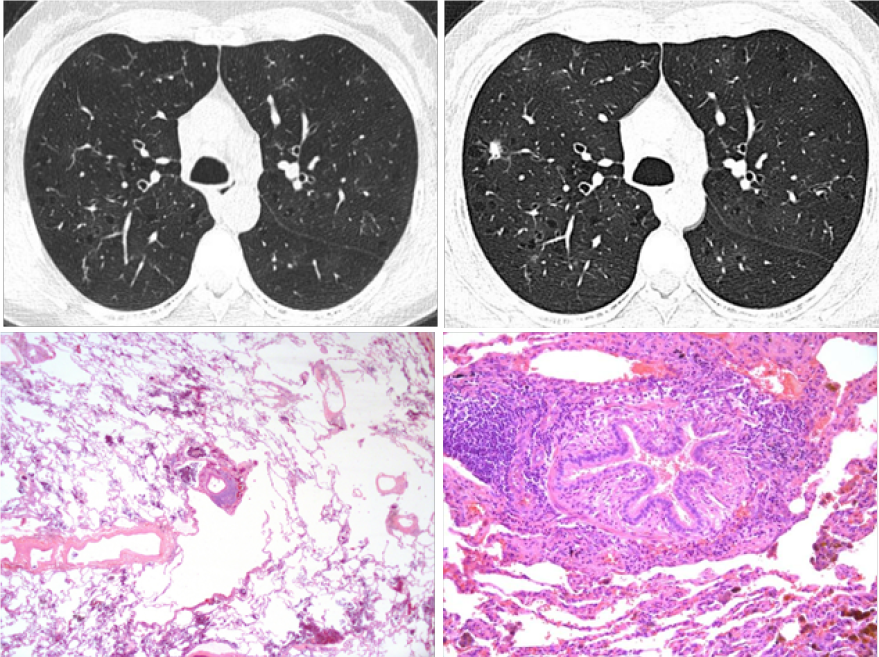

La TCAR evidenció múltiples quistes de distribución difusa, parches en vidrio deslustrado y atenuación en mosaico en la fase espiratoria. (Figura 1. A).

Durante el seguimiento, se identificó un nódulo pulmonar de bordes irregulares y vidrio deslustrado perilesional, localizado en el lóbulo superior derecho (Figura 1. B). Se realizó una segmentectomía anatómica del segmento anterior con disección ganglionar mediante cirugía toracoscópica asistida por video (VATS). El estudio histopatológico descartó malignidad y confirmó el diagnóstico de bronquiolitis folicular (Figura 1. C y D) que se clasificó como idiopática ya que no se identificó una etiología primaria.

Figura 1.

Bronquiolitis folicular – (A y B). Se observa un nódulo pulmonar (flecha) de bordes irregulares, acompañado de múltiples quistes de distribución difusa (puntas de flecha). Tinción de hematoxilina-eosina (C y D) muestra parénquima pulmonar con escasos cambios y bronquiolos terminales (BT) con nódulos linfoides peribronquiolares (flechas).